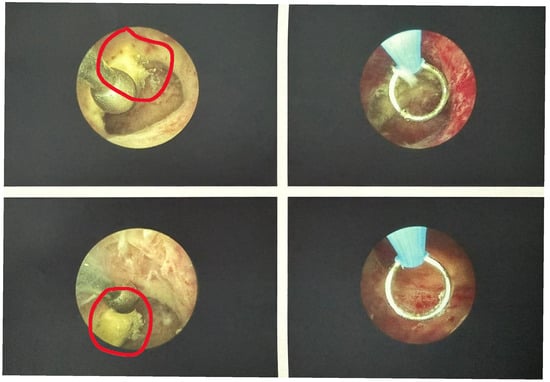

During a routine follow-up visit four months after delivery, her referring gynecologist performed a transvaginal ultrasound that revealed a hyperechoic endometrial lesion measuring 13 × 10 × 14 mm, located in the right lateral portion of the uterine cavity. Color Doppler evaluation demonstrated minimal vascularity (color score 1, minimal Doppler vascularity), consistent with retained amniochorionic tissue rather than vascularized RPOC (Figure 1). These features—small size, minimal vascularity, and late postpartum presentation—were considered favorable for an office hysteroscopic approach.

Figure 1. Transvaginal ultrasound image showing a hyperechoic, avascular lesion (circled) in the right lateral uterine wall.